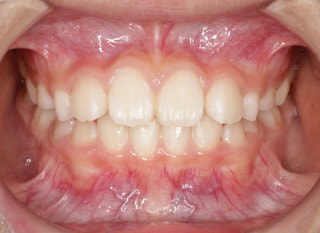

治療前